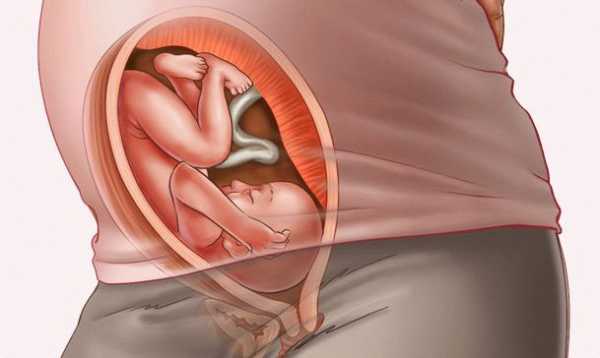

Ребенок на 29 неделе беременности настолько крупный, что уже не может крутиться в мамином животе, как

Начиная с этой недели малыш начинает набирать вес за счет того, что у него идет быстрое накопление прослойки подкожного жира. На сроке двадцати девяти недель ребенка можно сравнить со средним кочаном капусты. Он весит 1250 граммов, а его рост составляет 37 сантиметров. На данном этапе ему становится тесновато в матке, а ведь еще несколько месяцев назад он могу свободно кувыркаться, ворочаться и двигаться с одного края своего домика в другой.

Чтобы оценить темпы развития ребенка, узист проводит замеры лобно-затылочной доли, окружности головы, живота и изучает бипариетальные параметры. На мониторе врач смотрит положение малыша и определяет, занял ли он необходимую для рождения позу.

Зачастую малыш уже перевернулся головой вниз, готовясь пройти через родовые пути.

Также строго по показаниям проводится УЗИ на 29 неделе. Исследование назначается в том случае, если врач хочет убедиться в правильном внутриутробном развитии плода. Для оценки темпов развития ребенка диагност измеряет такие показатели, как бипариетальный и лобно-затылочный размеры, окружность головы и живота и др. На УЗИ специалист непременно определит положение, которое плод занимает в утробе матери. В большинстве случаев малыш уже перевернулся головой вниз, готовясь к выходу через родовые пути.

Вашему сыну или дочке с каждым днем становится все теснее и теснее. Потому Вы можете ощутить как изредка выпячиваются его ручки или ножки. На этой неделе рост Вашего малыша уже почти 35-40 сантиметров, а вес достигает 1200-1250 граммов. Размер от копчика до темени может составлять приблизительно 26 сантиметров. Он уже словно капуста или кабачок.

В большинстве случаев к этому периоду ребенок принимает правильное положение – головой вниз. Таким образом он будет проходить через родовые пути в процессе своего рождения.

Ребенку на 29 недели беременности уже достаточно сложно переворачиваться в матке, так как он занимает практически все свободное пространство. Часто на 29 неделе малыш располагается в предродовом положении — головой вниз. В то же время, ребенку хочется физической активности и он, по возможности, переворачивается, доставляя маме ощутимые удары.